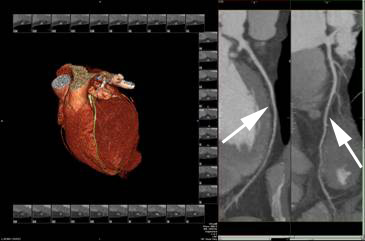

Normalt hjerte-CT uden forandringer i kranspulsårerne (stenose i koronararterierne). Kranspulsårer efter elektronisk rekonstruktion er markeret med pile.